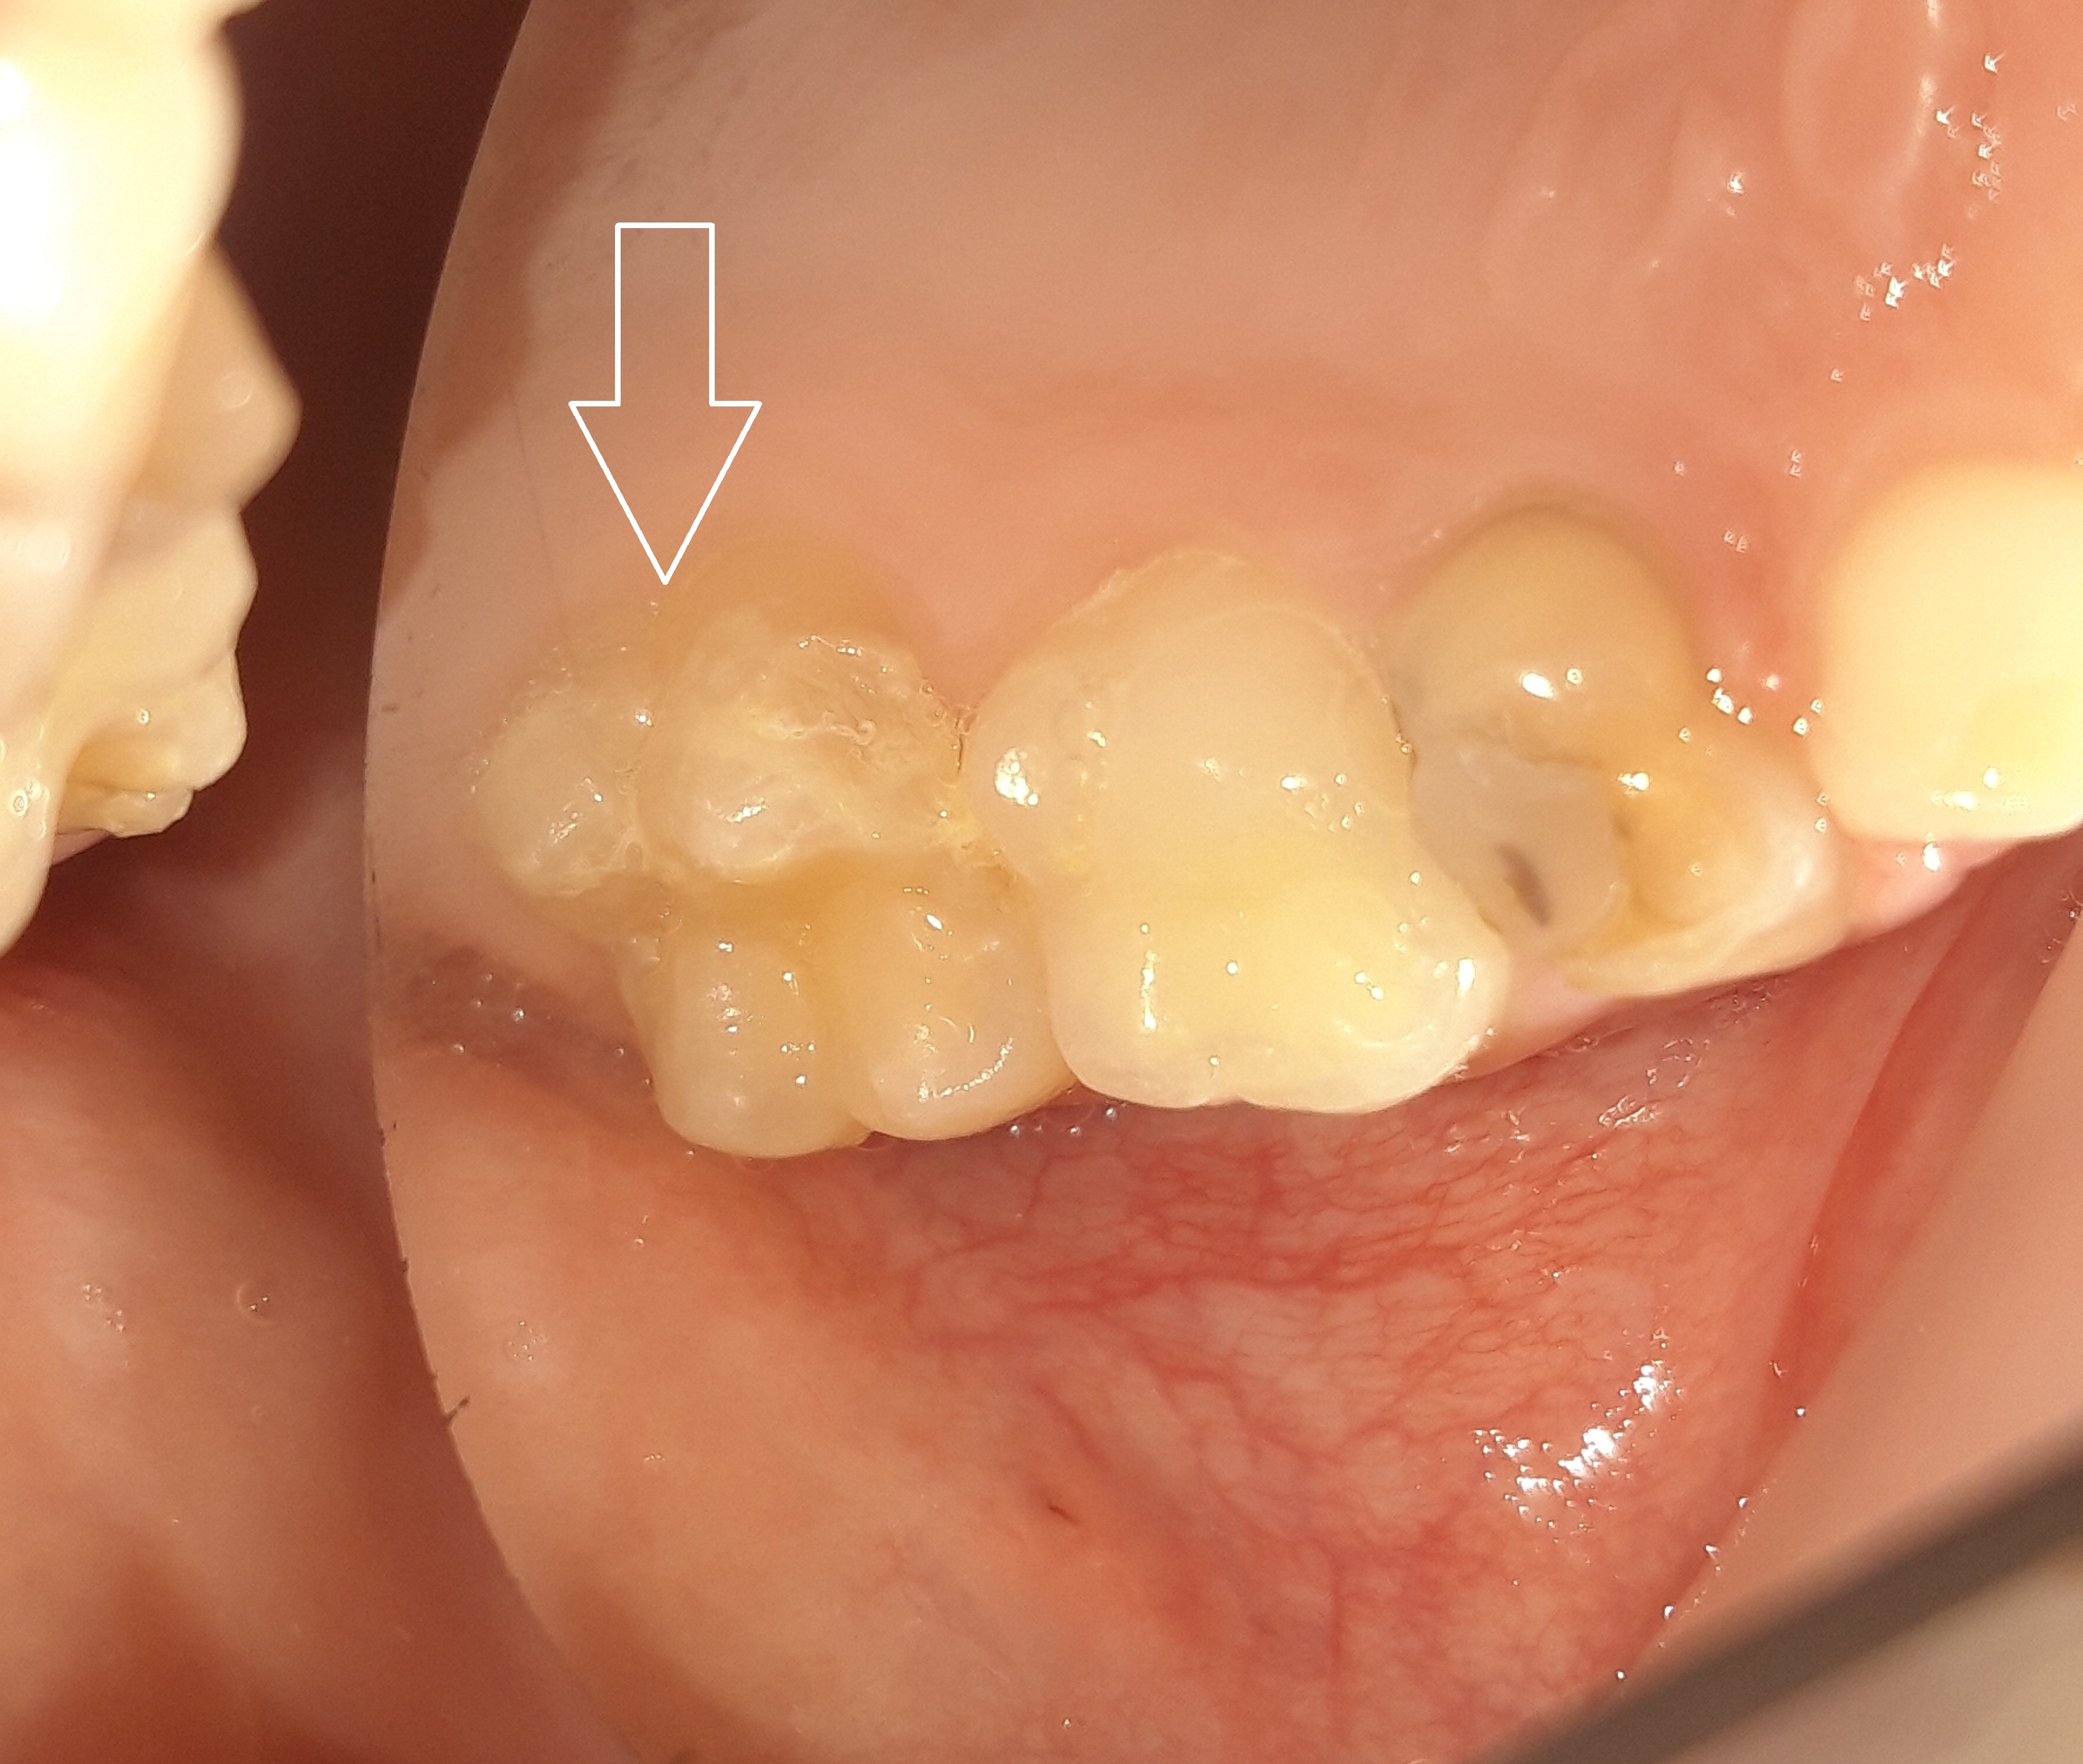

Στα πλαίσια του τυπικού οδοντιατρικού ελέγχου διαπιστώθηκε η ύπαρξη μιας μικρής τερηδονικής κοιλότητας στον πρώτο αριστερό μόνιμο γομφίο. Αποφασίστηκε η αφαίρεση της επιφανειακής αρχόμενης τερηδόνας και προληπτική κάλυψη οπών και σχισμών (sealant) στη μασητική επιφάνεια του μόνιμου άνω αριστερού πρώτου γομφίου.

Περιστατικά – Sealant / προληπτική κάλυψη οπών και σχισμών